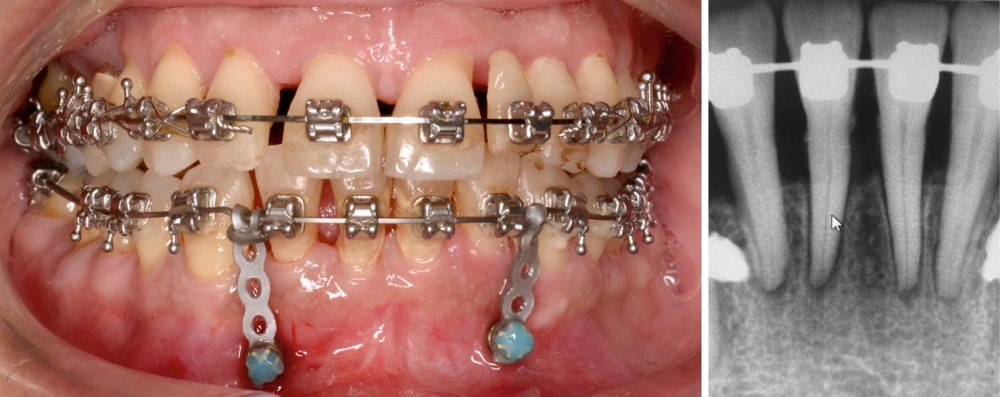

En raison de l’ancrage dentaire postérieur mandibulaire très limité, il est décidé d’utiliser des ancrages osseux pour l’ingression du bloc incisivo-canin mandibulaire, afin de niveler l’arcade et de recréer le surplomb nécessaire à la fermeture des diastèmes maxillaires. Deux minivis d’ancrage sont positionnées entre les dents 32/33 et 42/43, après réalisation d’un examen CBCT localisé sur l’arcade mandibulaire (fig. 7 et 8). Ces minivis antérieures ont été rapidement déposées, en raison de leur mobilité et de la gêne importante de la patiente liée au positionnement très apical du fait de l’alvéolyse.

Des minivis d’ancrage sont alors positionnées entre les dents 34/35 et 44/45 (fig. 9). Un sectionnel d’ingression antérieur (acier .018x.025) est fixé sur celles-ci, tout en passant par des tubes en croix situés entre les prémolaires afin d’éviter le dévissage des minivis. L’ingression est réalisée via des ligatures reliant l’arc orthodontique principal (TMA .018x.025 avec boucles double-delta) au sectionnel, selon une direction permettant l’ingression tout en limitant la composante de vestibulo-version. Du stripping mandibulaire a été réalisé de mésial de 33 à mésial de 43 afin de corriger l’indice de Bolton.

La contention collée de fin de traitement a consisté en plusieurs fils TMA .016 étendus jusqu’aux premières prémolaires, afin de limiter la mobilité des dents antérieures et empêcher la réouverture des diastèmes. Ces fils ont été modélisés numériquement et pliés par robot (société Winnove Medical, Rennes, France), permettant de s’assurer de l’absence de visibilité des fils dans les espaces inter-dentaires et limiter les prématurités occlusales (fig. 14). Des gouttières de contention thermoformées sont réalisées en cas de casse ou décollement des fils, afin de prévenir une éventuelle réouverture des diastèmes.